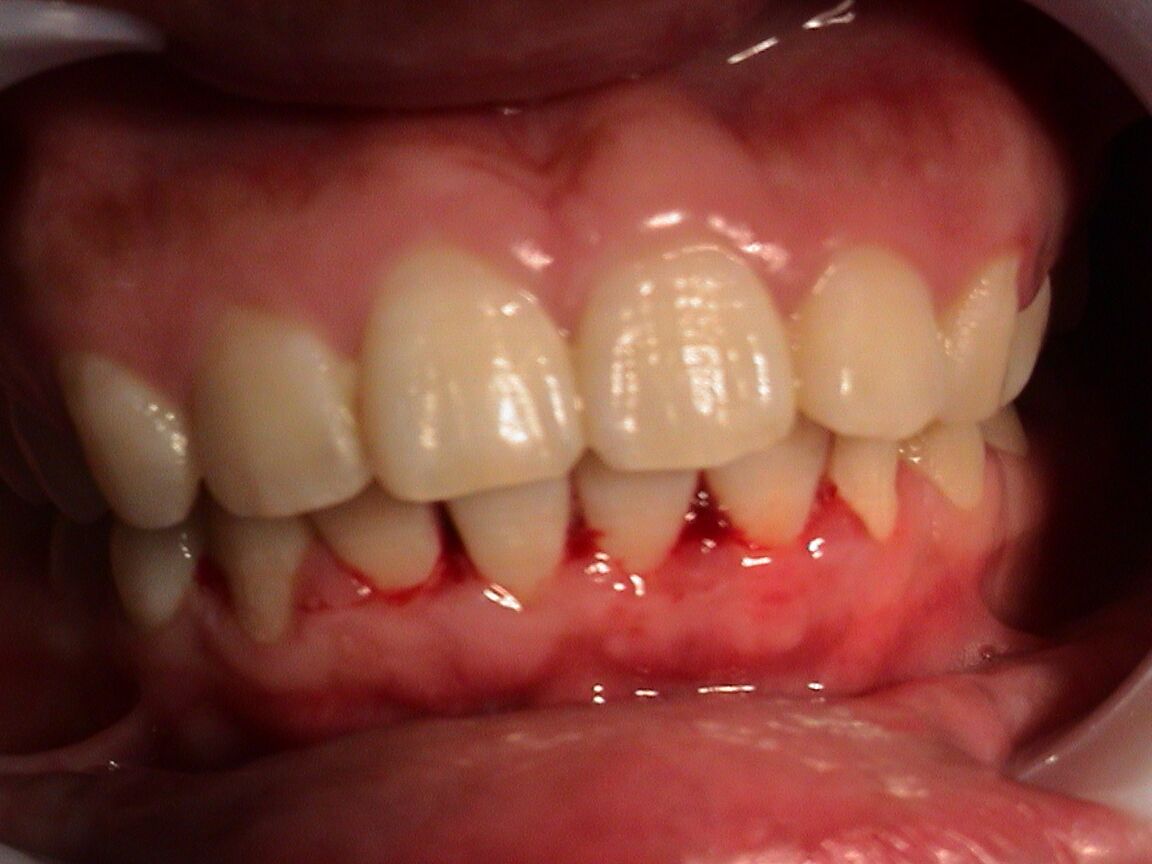

牙龈出血不止的原因很多,可以将牙龈出血的原因分为两个方面:方面是口腔局部因素引起的牙龈出血,如牙龈炎、牙龈瘤等。另方面是全身性疾病表现的牙龈出血,如贫血、白血病血友病等。

1、口腔局部因素引起: 多是由于口腔不清洁,食物残渣、牙垢、牙石经常堆积在牙体周围,口腔内的细菌在此大量的进行繁殖,导致牙龈炎而发生牙龈出血,这种原因引起的牙龈出血,常常伴有口臭。

3、其他牙龈疾病引起: 由于血管异常丰富,在嚼东西时,瘤体因摩擦而溃破,也可引起出血。其他如刷牙方法不正确、残根、残冠、制作不良的牙套、不良充填物等锐利的边缘刺激牙龈肿胀发炎均可引起牙龈出血。